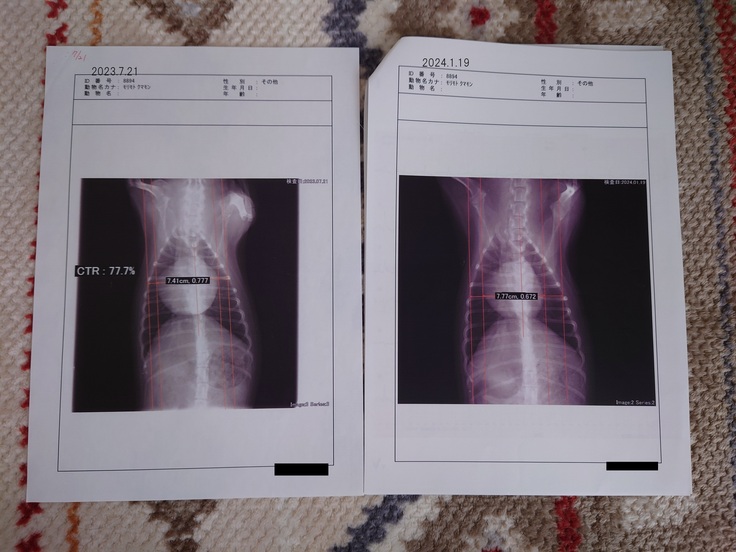

心臓の大きさですが、最初に検査をしていただいた2023年7月21日と比べると

明らかに小さくなってきております。

レントゲン画像 左:2023/7/21 右:2024/1/19